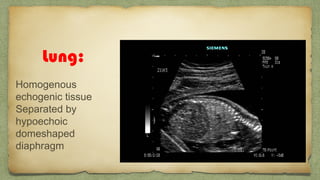

Lung:

Homogenous

echogenic tissue

Separated by

hypoechoic

domeshaped

diaphragm

Hypoechogenic structure

other than heartโ€ฆ.

CCAM

Pul Hypo

CDH

Pl effusion